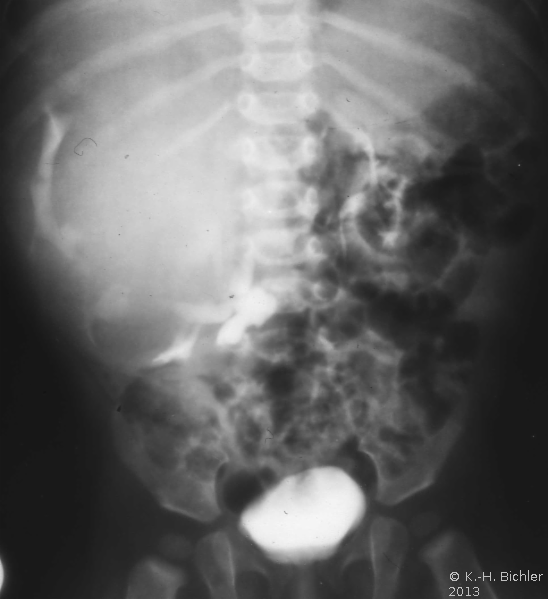

Die abdominale Sonographie bzw. die Computertomographie haben die Ausscheidungsurographie als die bildgebende Untersuchungstechnik bei Patienten mit Oberbauchtumor, z.B. Wilmstumor, verdrängt. Einige Ausscheidungsurographien von Kindern mit Wilmstumoren aus unserer Sammlung aus den 70er Jahren des vergangenen Jahrhunderts sind aus didaktischen Gründen hier wiedergegeben. Die Bilder zeigen instruktiv die Größe und Verdrängung durch den Tumor (

4 Abbildungen HG1).